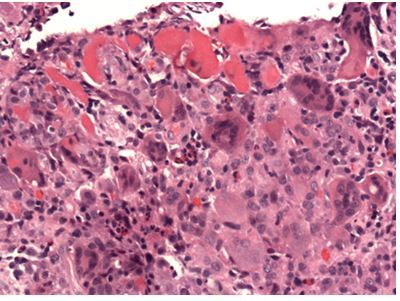

What type of myocarditis is being shown here and how can you tell?

A

Rheumatic myocarditis which is a pancarditis

The picture is showing Anitschkow cell from an Aschoff nodule—

fibrinoid necrosis of heart muscle

– Anitschkow cell (histiocytes with condensed chromatin give caterpillar like appearance)

– Aschoff cells (MN giant cells)

– Collagenolysis